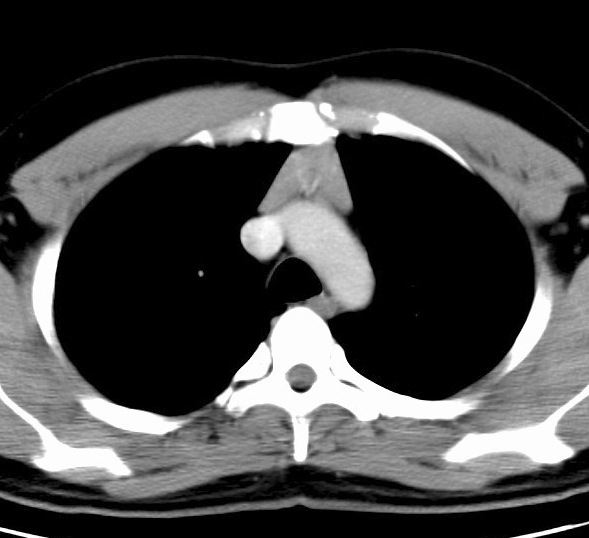

Case 5 Thymic hyperplasia

Thymic hyperplasia